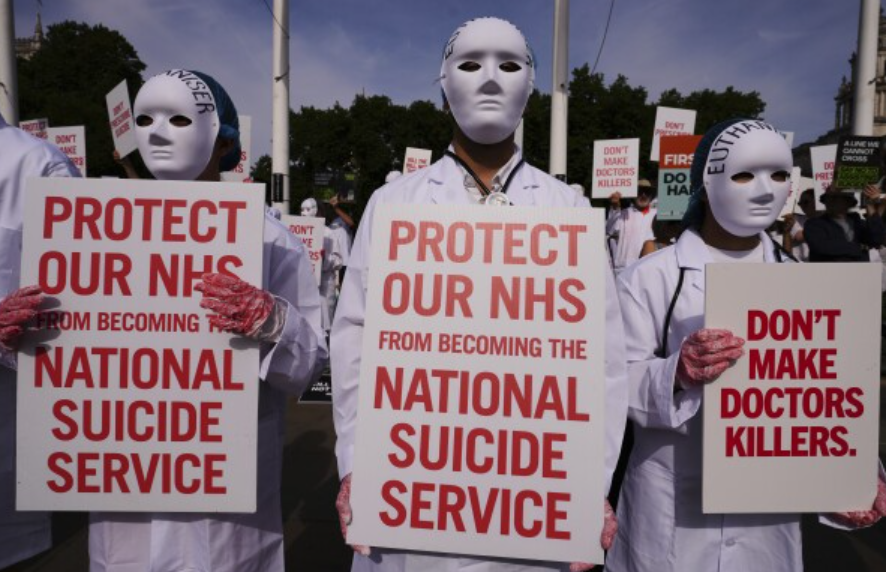

The Emergence of the National Dealth Service

In an age in which the Government is threatening to pay more for death-by-medicine than for life-by-medicine, the National Health Service should be renamed the National Dealth Service, says Professor James Alexander.

The Coalition Against Killing

It's been a dark week in the UK, with the Commons approving both abortion up to birth and assisted suicide via poisoning on the NHS. Dr Clare Craig was outside Parliament on Friday and sees reasons not to lose hope.